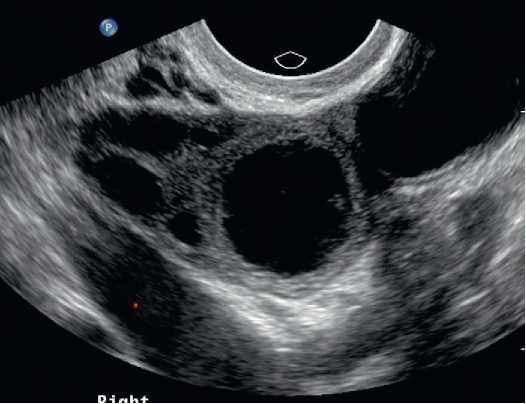

Your doctor can detect an ovarian cyst during a routine pelvic examination. They may notice swelling on one of your ovaries and order an ultrasound test to confirm the presence of a cyst. An ultrasound test (ultrasonography) is an imaging test that uses high-frequency sound waves to produce an image of your internal organs. Ultrasound tests help determine the size, location, shape, and composition (solid or fluid filled) of a cyst.

Ultrasound device: an imaging device used to visualize the ovary.